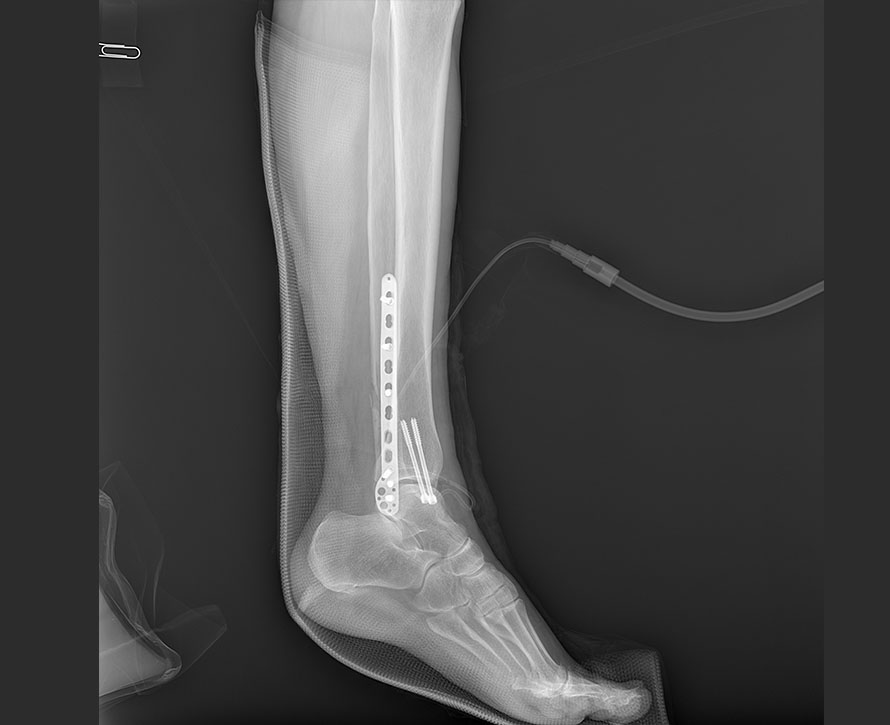

臨床圖像